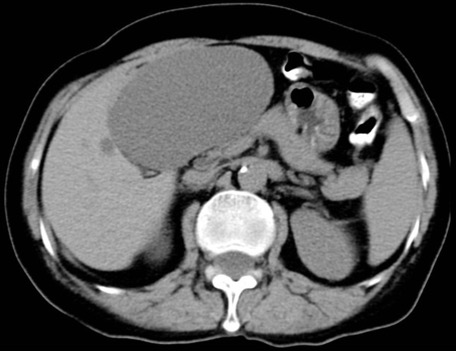

Caratteristiche TC

L’ascesso presenta due segni caratteristici

- Cluster sign: distribuzione segmentaria a grappolo

- Target sign: aspetto trilaminato con ipodensità centrale (necrosi), rim iperdenso (reazione flogistica di parete), vallo esterno ipodenso (edema perilesionale)